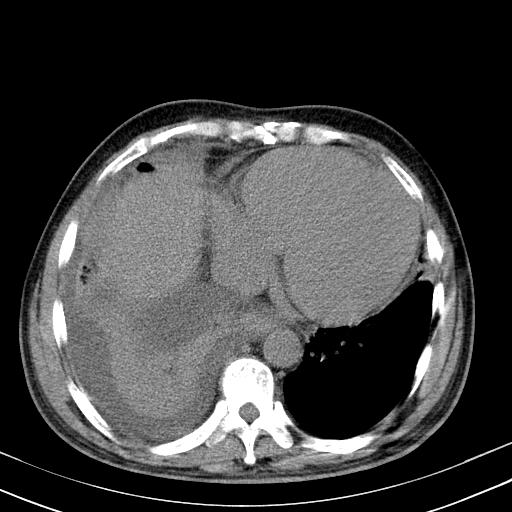

以下是引用zxl51642在2010-3-21 17:06:00的发言:[br]右下中心型肺癌并阻塞性肺炎/不张,纵膈淋巴结肿大,右侧大量胸腔积液,左侧少量胸腔积液,少量腹水。建议纤维支气管镜进一步检查。